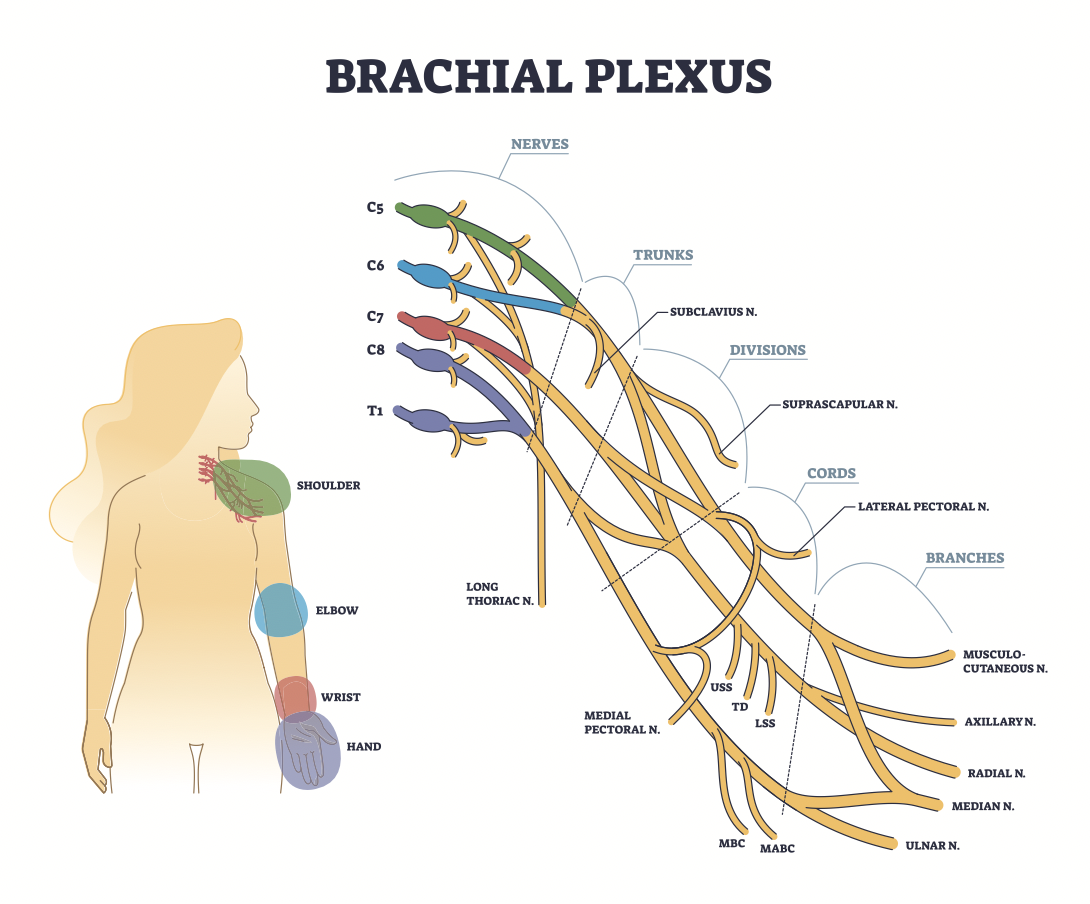

手部治疗中胸廓出口综合征 (TOS) 测试的敏感性和特异性

作者:Mikayla Murphy 手部疗法中胸廓出口综合征 (TOS) 测试的敏感性和特异性 胸廓出口综合征 (TOS) 描述了神经、动脉的受压,...